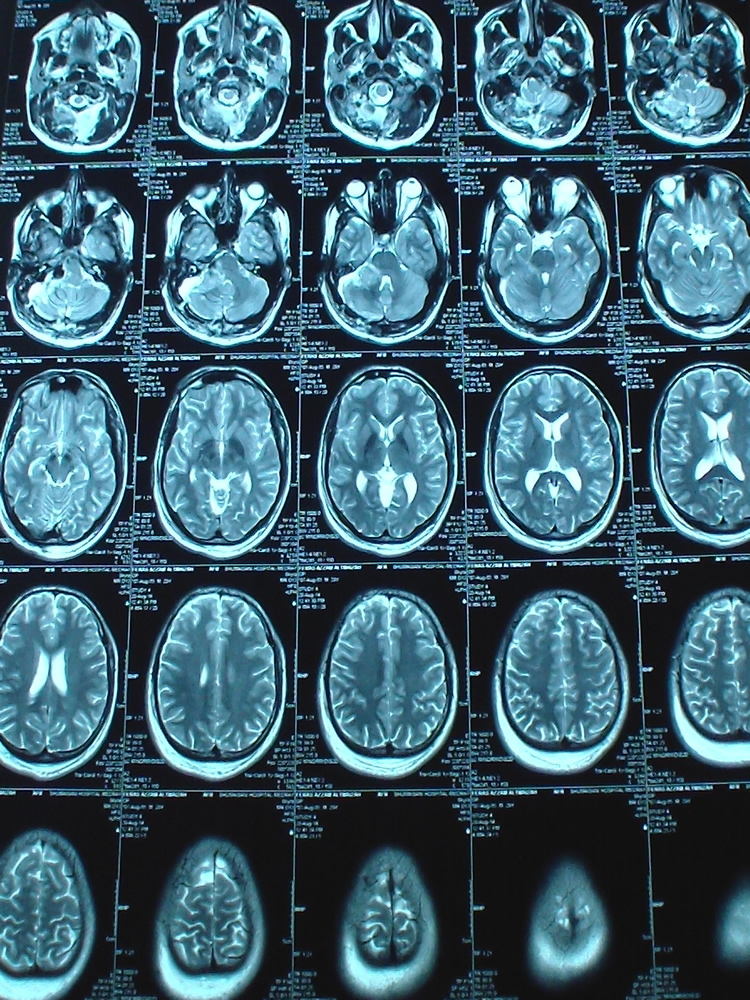

17-AUGUST-2014  FIRAS AZZAM AL-TMEZEH  29 YEARS  BILATERAL ACOUSTIC SCHWANNOMAS WITH PROGRESSING RIGHT SIDE.

The patient came to the clinic 09-January-2010 complaining of V1 pain for one month and decreased hearing right ear for 2 years. MRI of the brain performed 05-January-2010 showed right acoustic schwannoma extending to the brain stem and left intracanalicular one. Audiometry done 07-January-2010 confirming practical hearing loss in the right side. Tegretol was started and the patient came 14-April-2010 telling that he was neuralgia free with medication and the pain resumed when he stopped it. The patient was advised to keep in medication and to be followed later. The patient came 19-July-2010 with MRI of the brain done 18-July-2010 showing the same tumors sizes and the neuralgia is not present. The patient came several times over the years and he was reluctant for surgery. The last time he came 07-August-2014 and sent for new MRI which was done the same day. There is enlargement of the right acoustic schwannoma, compressing the brainstem. The right mass 25x19x17 mm  and the left 20x10x9 mm.

Figure-1: Axial TW2 done during surgery showing the removal of the residual mass which was stuck to the pontomedullary junction.

Figure-2: The intraoperative TW1 MRI showing the clearance of the right acoustic schwannoma without any edema or infarction at the resected last part f the tumor.